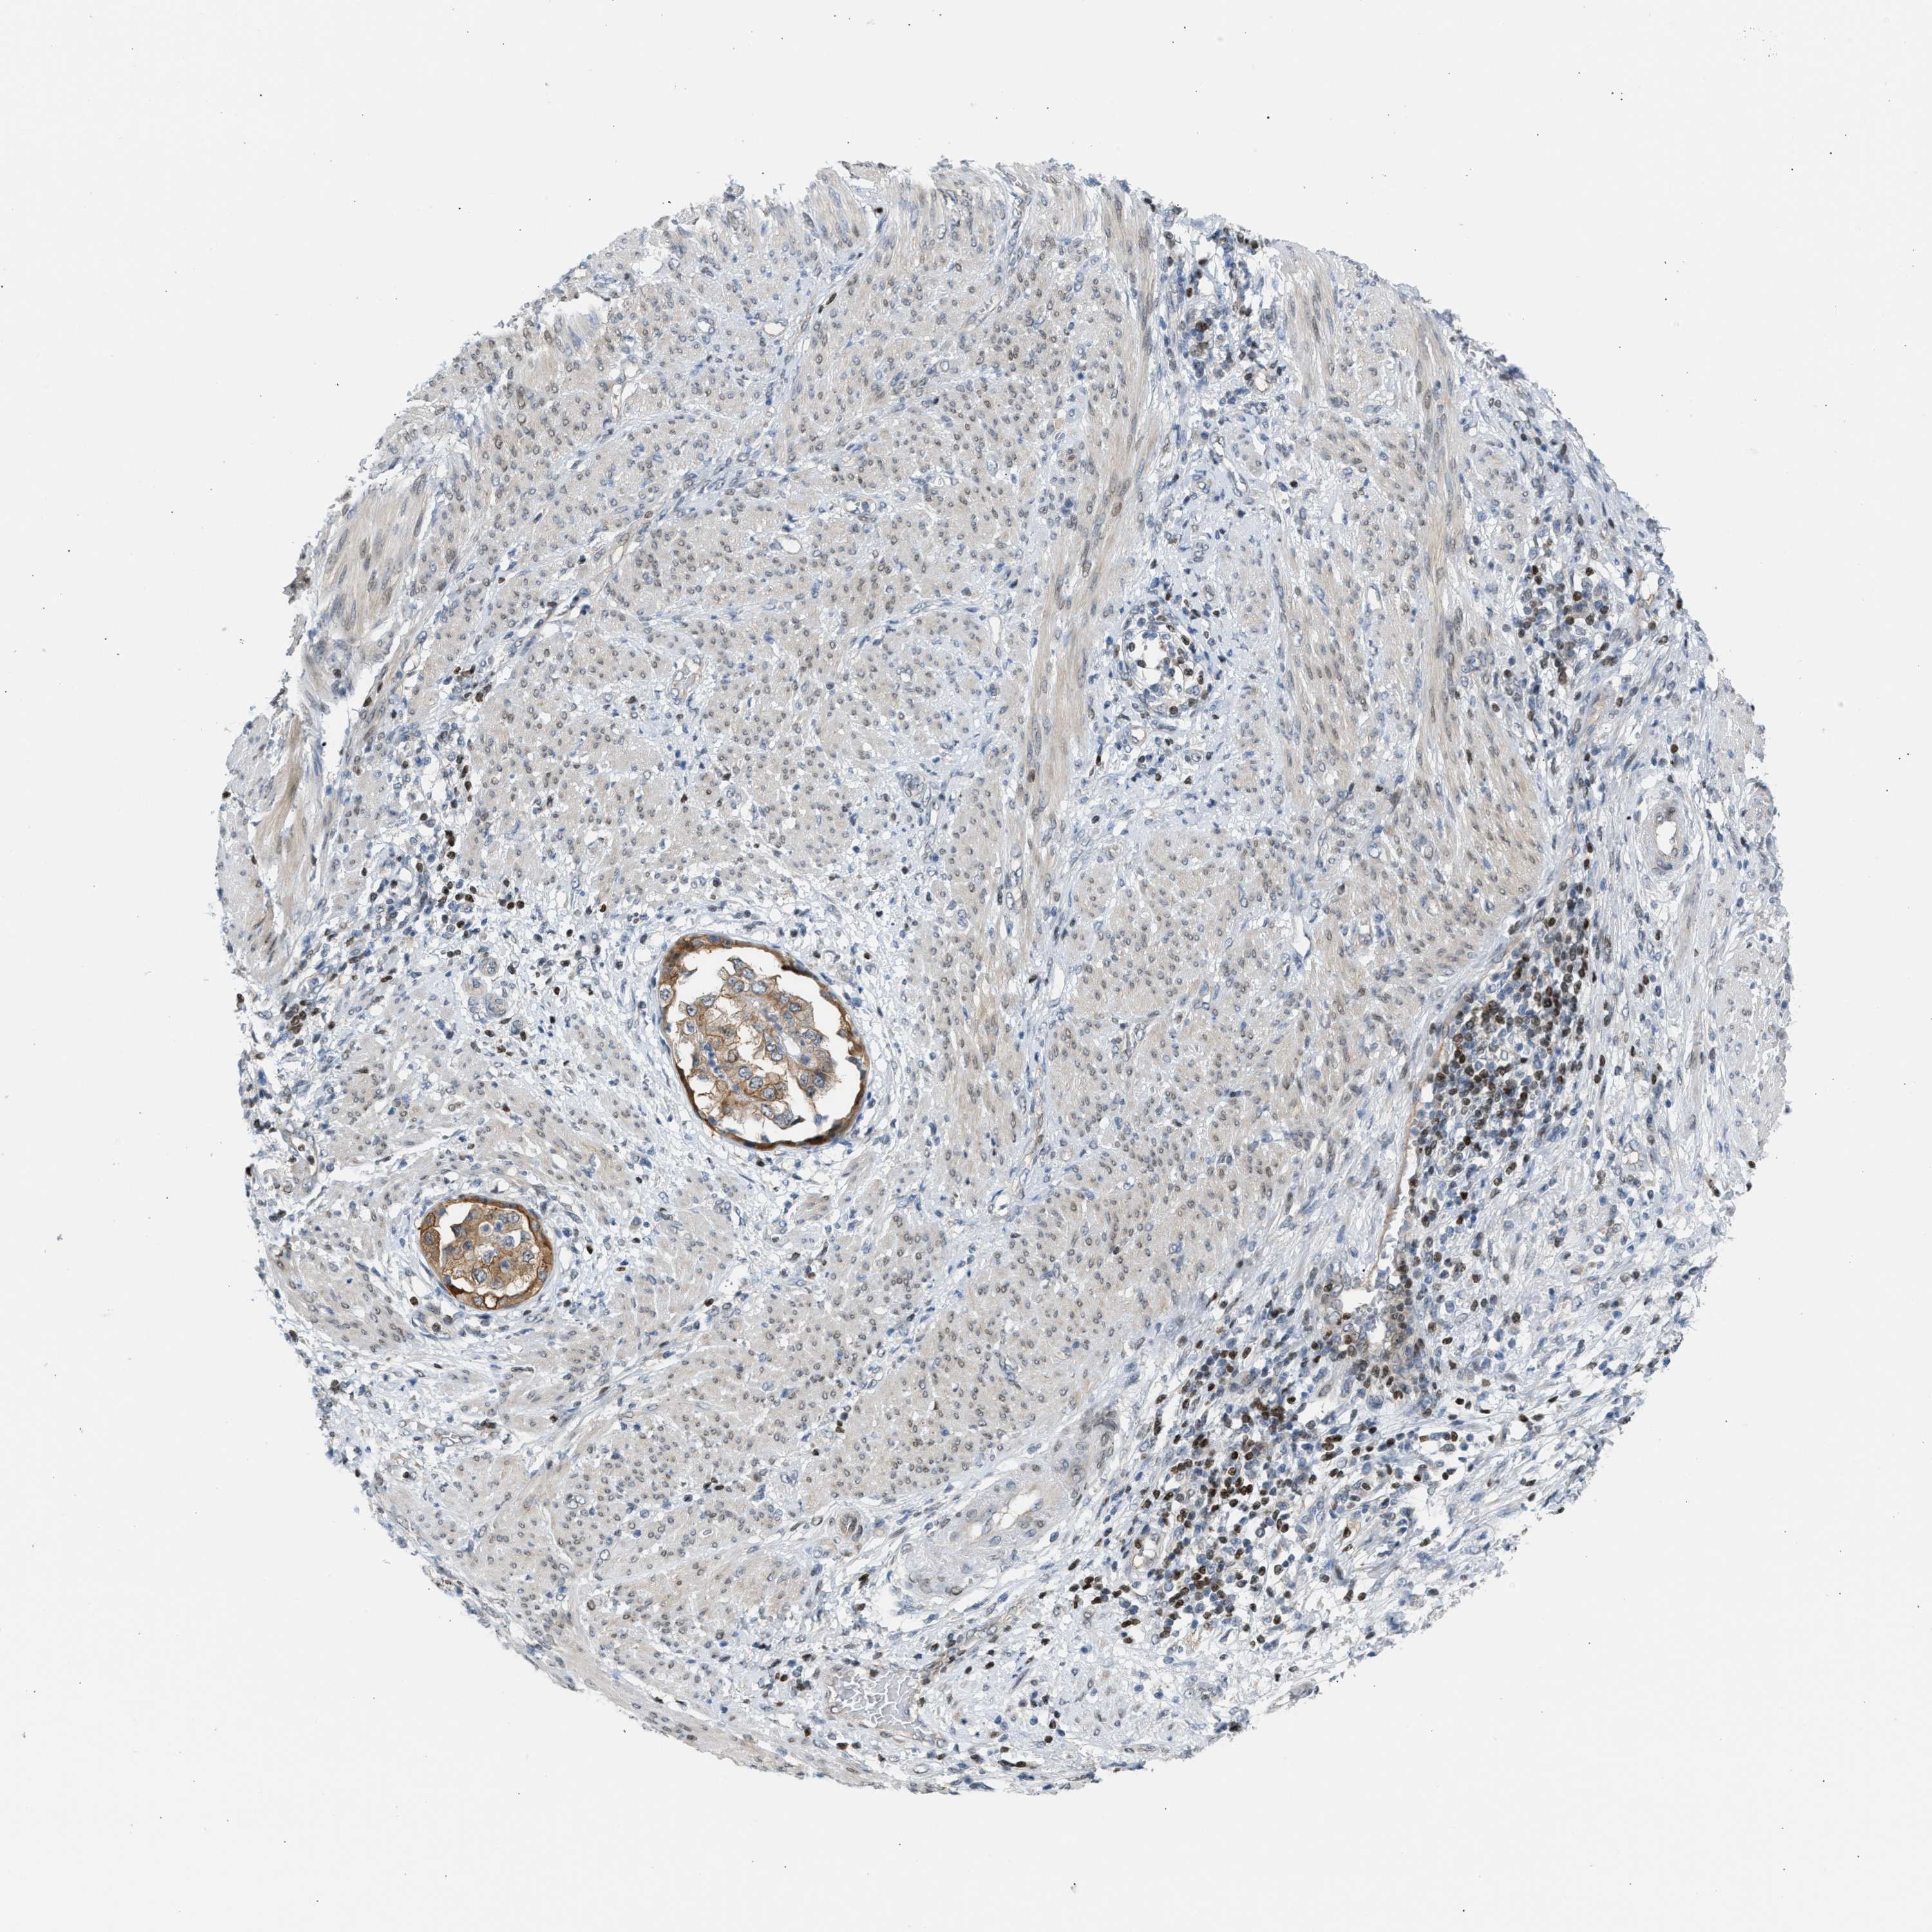

ENDOMETRIAL CANCER - Protein expressioni

A mouse-over function shows sample information and annotation data. Click on an image to view it in a full screen mode. Samples can be filtered based on level of antibody staining by selecting one or several of the following categories: high, medium, low and not detected. The assay and annotation is described here.

Note that samples used for immunohistochemistry by the Human Protein Atlas do not correspond to samples in the TCGA dataset.

Antibody stainingi

Antibody staining in the annotated cell types in the current human tissue is reported as not detected, low, medium, or high, based on conventional immunohistochemistry profiling in selected tissues. This score is based on the combination of the staining intensity and fraction of stained cells.

Each image is clickable and will lead to virtual microscopy that enables deeper exploration of all samples and also displays staining intensity scores, fraction scores and subcellular localization as well as patient and tissue information for each sample.

Antibody CAB020139

Staining

High

Medium

Low

Not detected

Intensity

Strong

Moderate

Weak

Negative

Quantity

>75%

75%-25%

<25%

None

Location

Nuclear

Cytoplasmic/membranous

Cytoplasmic/membranous,nuclear

Adenocarcinoma, NOS